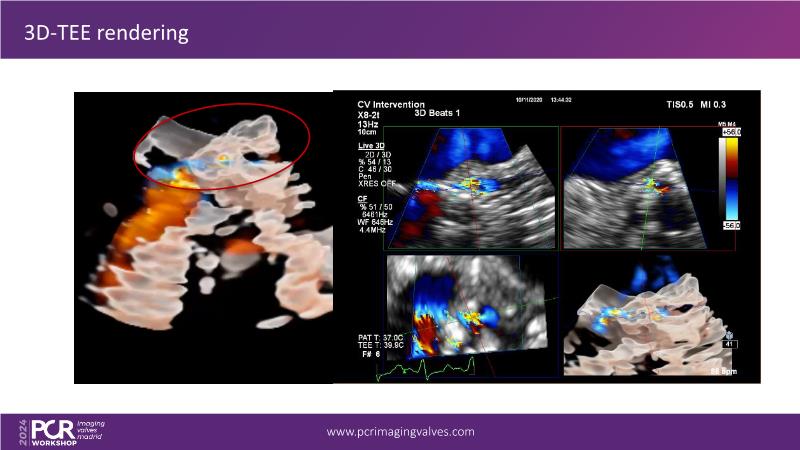

Explore cutting-edge transcatheter valve interventions for mitral and aortic valve disorders, including valve-in-valve procedures and management strategies for paravalvular leakages, and learn about diagnosing and treating mitral annular calcification and transcatheter options in infective endocarditis.

- To get tips and tricks for guidance of transcatheter intervention